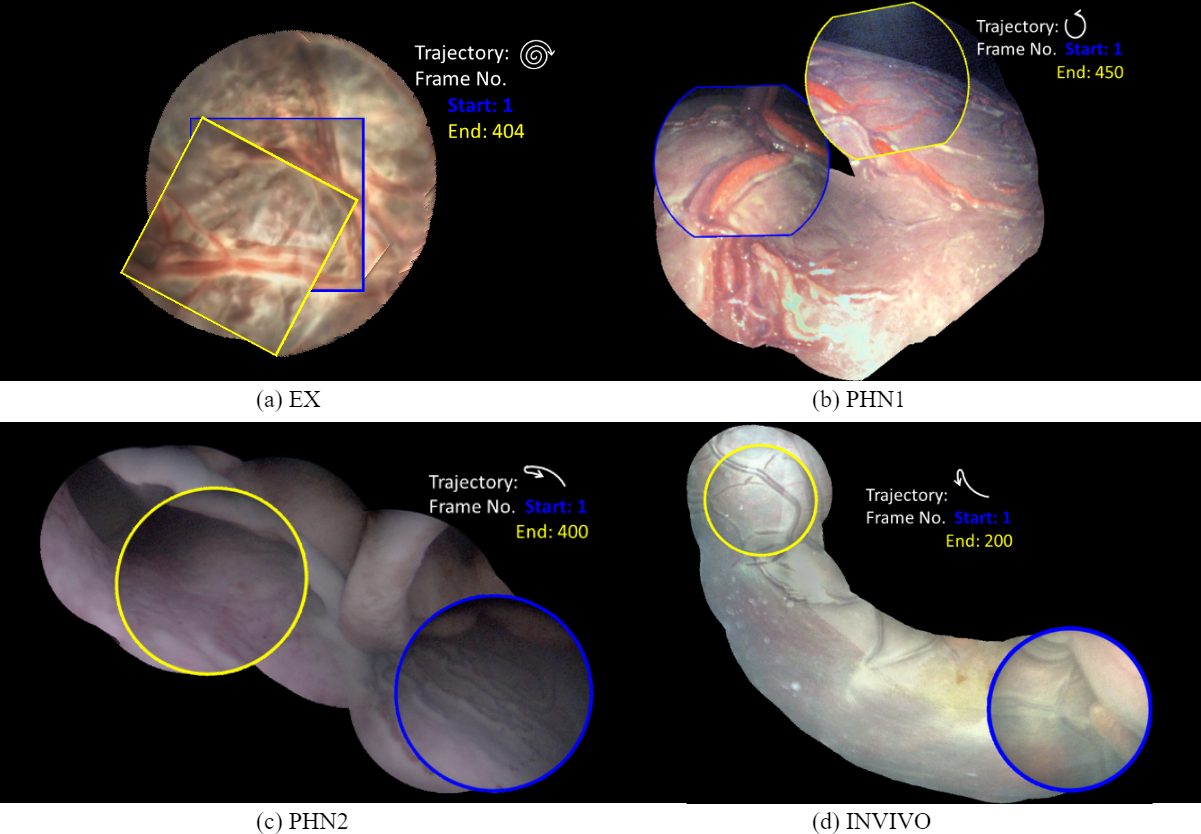

For experimental analysis, we use 5 fetoscopic videos (Table. 1), which include a synthetic video (SYN) - a discontinuous version of this sequence was used in [11], an ex-vivo in water (EX) data reported in [5], a placenta phantom (PHN1), a TTTS phantom111TTTS phantom from Surgical Touch Simulator: https://www.surgicaltouch.com/ in water (PHN2) depicting an in-vivo procedure and an in-vivo TTTS procedure (INVI). Note from Table. 1 the variability in visual quality, appearance, resolution, imaging source, camera views and captured motion. These variations pose challenging scenarios for mosaicking methods.

The visualization and comparison results on one circular loop (360 frames) of the SYN sequence are shown in Fig. 3(a)-(c). Note the small drift in DSM compared to FEAT. Similar behavior is observed from the mean residual error in Fig. 3(d) where the errors are reported for FEAT, DIH and DSM for the complete length of the sequence (811 frames). It can be seen that the error for FEAT starts increasing after approximately 300 frames and the mosaic starts drifting away. DIH error explodes within a few frames due to the random perturbation during training (Sec. 2). On the other hand, the error for DSM is very small and remains bounded. This is further verified from the low RMSE (0.36) and photometric (2.48) errors for DSM (Fig. 4). Comparison of our proposed DSM with FEAT and DIH is presented in Fig. 4. Overall the pairwise homography errors are high for FEAT for all five sequences due to poor visual quality and lack of texture in the fetoscopic videos. The RMSE and photometric errors for DIH are low compared to FEAT but are always higher compared to DSM (e.g. RMSE on EX for DIH (1.64) and DSM (0.38)). In DIH, this error accumulated over time during mosaic generation and resulted in a large drift. For EX, PHN1, PHN2 and INVI sequences, the average RMSE errors are 0.38, 0.32, 0.35 and 0.34, and photometric errors are 0.98, 1.76, 1.52, 2.42, respectively.

Mosaics generated using the proposed DSM for the EX, PHN1, PHN2 and INVI sequences are shown in Fig. 5. These mosaics are best assessed in the supplemental video that shows the qualitative comparison with respect to FEAT and DIH. DSM created a meaningful mosaic for EX (unseen data) with minimum drift accumulation over time which can be observed from the start and end frames in Fig. 5(a). PHN1 contained non-planar views without occlusions with a freehand circular trajectory. DSM generated reliable mosaics with minimum drift (Fig. 5(b)), however FEAT drifted away due to non-planar views, insufficient feature matches and long-range videos. PHN2 and INVI represent the most challenging scenarios containing highly non-planar views with heavy occlusions, low resolution and texture paucity. We observe from Fig. 5(c)(d) that although the generated mosaics can serve well for increasing the FoV, yet there is a noticeable drift due to highly challenging conditions. Such errors may be corrected by end-to-end training using the photometric loss [8].